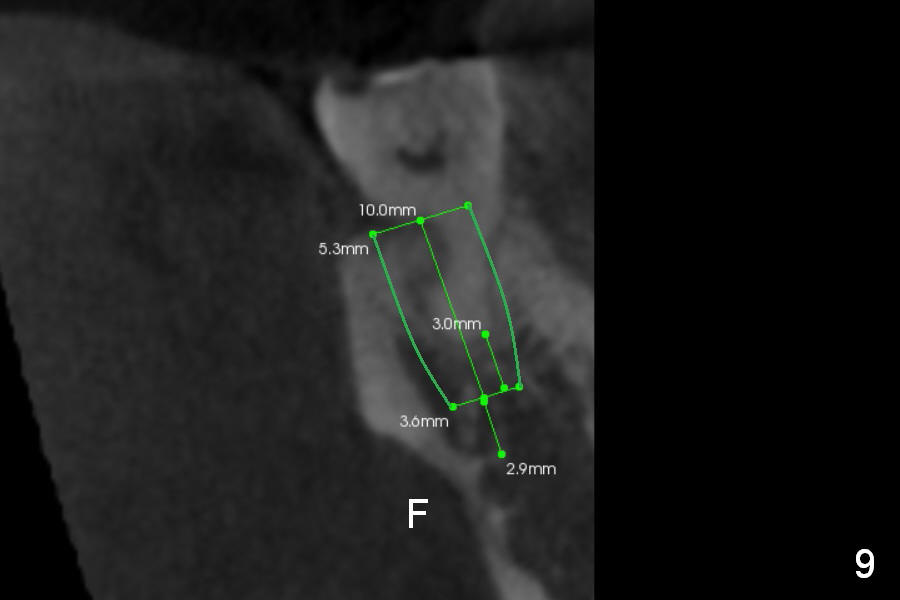

CBCT Analysis of the lower left 2nd molar reveals that the proper implant size is 5.3x10 mm (Fig.8-10). The root is C shaped; limiting factor is buccolingual width (5.5 mm, Fig.8 (axial section)). The major difference between #18 and 31 is the resorption of the buccal plate of the latter (traumatic extraction, Fig.9 (F: submandibular fossa)).